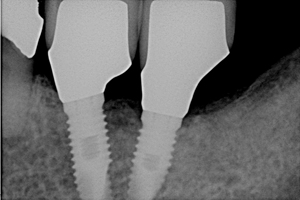

これはお口全体を撮影したパノラマレントゲン写真です。

向って見ていただいて

右下の奥にネジが入っていますよね。

これが、インプラントです。

骨の中にがっちり埋め込み強く固定されます。

拡大してみると

こんなネジです。

ある患者さんは3年前に他医院で下顎部分にインプラント治療をされました。

しかし、最近になってインプラントを埋入した部分が腫れて痛みが出るようになりました。

レントゲン写真を撮影し、詳しく骨の状態を拝見するとインプラントを埋入した周囲の骨が溶けてしまっていました。

バイ菌が入り込み炎症を起こしています。